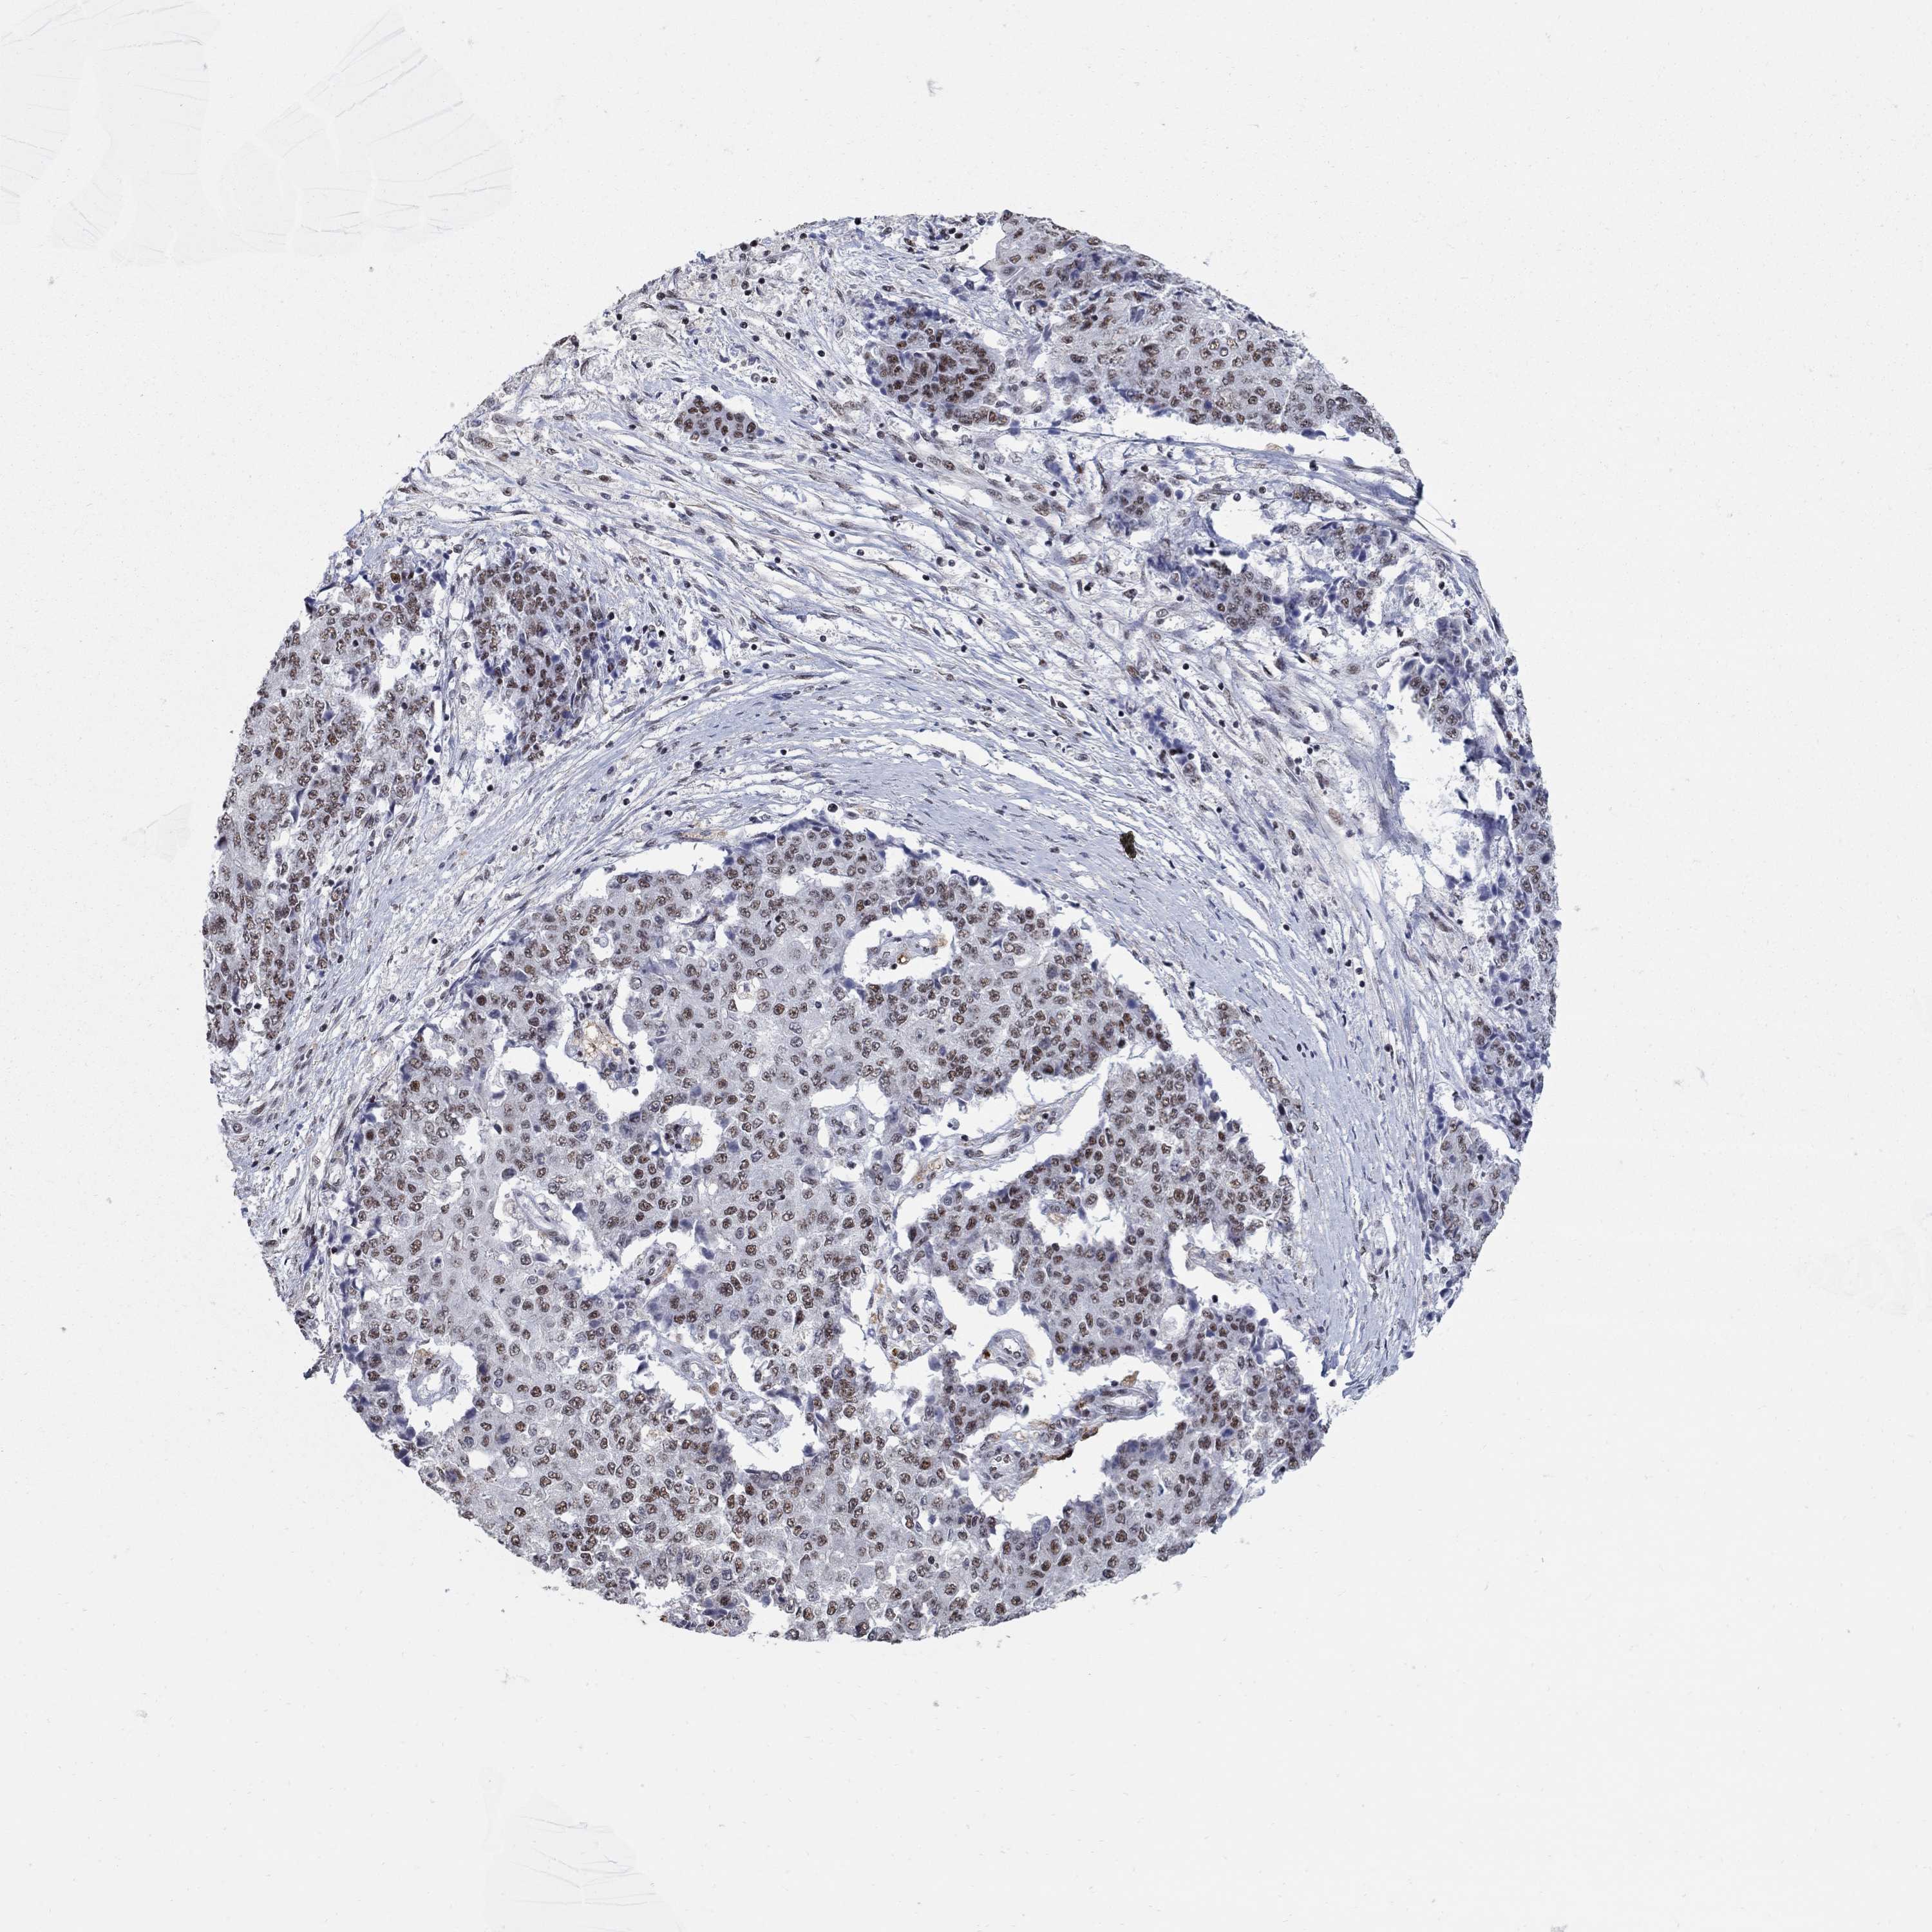

OVARIAN CANCER - Protein expressioni

A mouse-over function shows sample information and annotation data. Click on an image to view it in a full screen mode. Samples can be filtered based on level of antibody staining by selecting one or several of the following categories: high, medium, low and not detected. The assay and annotation is described here.

Note that samples used for immunohistochemistry by the Human Protein Atlas do not correspond to samples in the TCGA dataset.

Antibody stainingi

Antibody staining in the annotated cell types in the current human tissue is reported as not detected, low, medium, or high, based on conventional immunohistochemistry profiling in selected tissues. This score is based on the combination of the staining intensity and fraction of stained cells.

Each image is clickable and will lead to virtual microscopy that enables deeper exploration of all samples and also displays staining intensity scores, fraction scores and subcellular localization as well as patient and tissue information for each sample.

Antibody HPA075076

Staining

High

Medium

Low

Not detected

Intensity

Strong

Moderate

Weak

Negative

Quantity

>75%

75%-25%

<25%

None

Location

Nuclear

Cytoplasmic/membranous

Cytoplasmic/membranous,nuclear

Cystadenocarcinoma, serous, NOS

Cystadenocarcinoma, mucinous, NOS

Carcinoma, endometroid